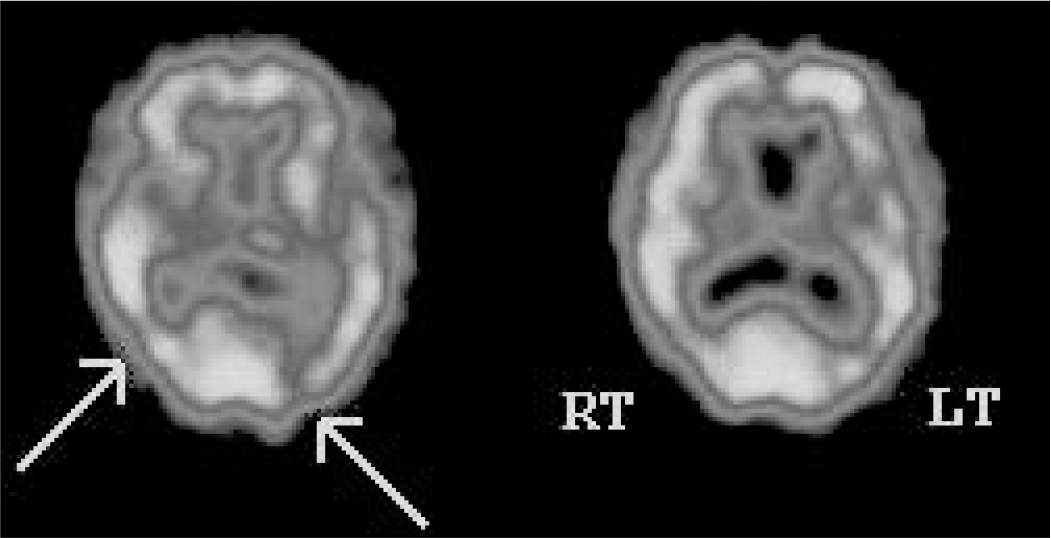

Technetium-99m HMPAO SPECT findings in vascular dementia reveal considerably reduced cerebral blood flow to certain brain areas compared with Alzheimer’s dementia; a typical SPECT scan is shown in Fig. 2. These brain regions include frontal lobes and the basal ganglia. Other studies have demonstrated reduced cerebral blood flow in bilateral thalami, anterior cingulate gyri, superior temporal gyri, caudate and left parahippocampal gyrus in patients with vascular dementia compared with controls (Reference Shim, Yang and KimShim 2006). However, SPECT is not routinely recommended in the investigation of dementia owing to a lower diagnostic accuracy than that of clinical guidelines; sensitivity is reported to be as low as 43% (Reference Shim, Yang and KimShim 2006).

FIG 2 Tc-99m HMPAO single-photon emission computed tomography findings in a patient with cognitive impairment. The scan shows patchy perfusion defects in temporal and parietal lobes bilaterally, with reduction in perfusion to the occipital lobes (right > left). These findings are in keeping with vascular dementia.